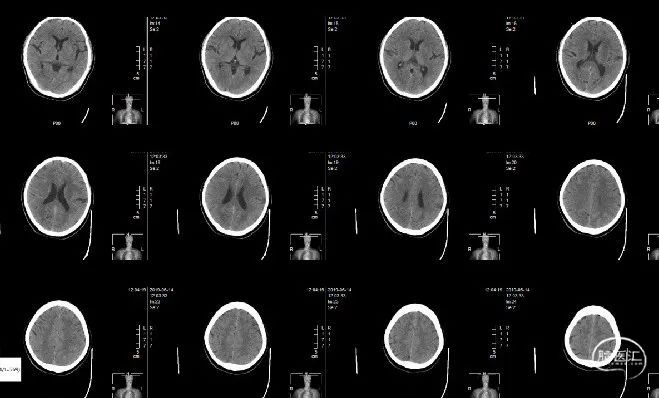

现病史:缘于入院5小时前(2018年4月23日12时10分)无明显诱因突发右侧肢体无力,右侧肢体完全不能动弹,伴口角歪斜,伴对答不能、理解障碍,无呕吐,无大小便失禁、人事不清,无吞咽困难、饮水呛咳、呼吸困难,急诊我院,行头颅CT未见新鲜梗塞灶及出血灶,未见致密征,发病前mRS 0分,发病后mRS 4分,ASPECTS评分10分,急诊拟“急性脑梗塞”收住院。本次患病以来,精神尚可,未进食及睡眠,大便未解,小便正常。

查体情况:NIHSS 16分;ASPECT评分10分。

右侧股动脉穿刺,穿刺至发病时间8小时。行全脑血管造影示:患者左侧颈内动脉闭塞(ICA),闭塞血管直径约3.1mm,TICI 0分,前交通、后交通均开放,右侧颈内动脉通过前交通代偿左侧大脑中动脉及左侧大脑前动脉供血区,左侧后交通开放,并左侧颈内动脉末端逆行显影,左侧大脑后动脉通过脑膜支部分代偿左侧大脑中动脉供血区。

术前对侧循环造影可见前交通动脉开放,左侧M1段有狭窄。

行椎动脉造影,可见后循环开放,血液可通过后交通动脉向大脑中动脉代偿。